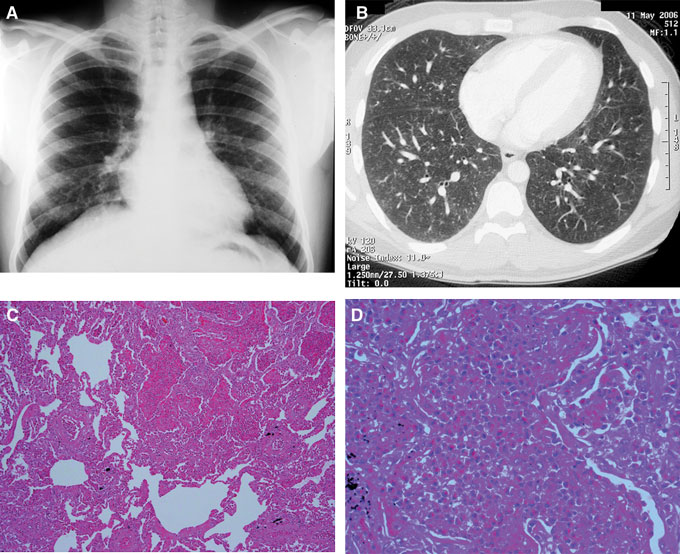

Η τροπική πνευμονική ηωσινοφιλία είναι ένα σπάνιο, αλλά καλά αναγνωρισμένο, σύνδρομο που χαρακτηρίζεται από πνευμονικές διάμεσες διηθήσεις και περιφερική ηωσινοφιλία.

Τα ακτινολογικά ευρήματα είναι μη ειδικά, με φυσιολογική εμφάνιση στην ακτινογραφία θώρακα σε έως και 20% των ασθενών. Οι υπόλοιποι έχουν πνευμονικές διηθήσεις.